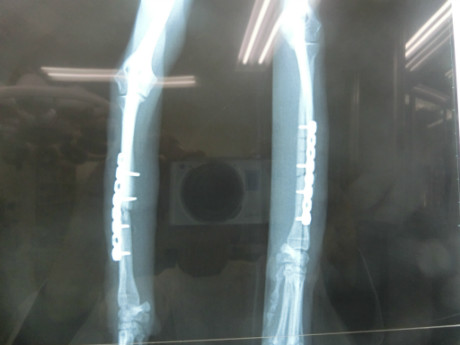

S.りんちゃん (橈尺骨骨折)

S.りんちゃんは、階段から飛び降りて、両前足を骨折しました。

二軒の病院で無理と言われ、当院を紹介されて、来られました。両前肢の橈骨尺骨が折れていました。

LCPプレートで手術しましたが、順調に回復し、今日は定期検査で元気に来院されました。